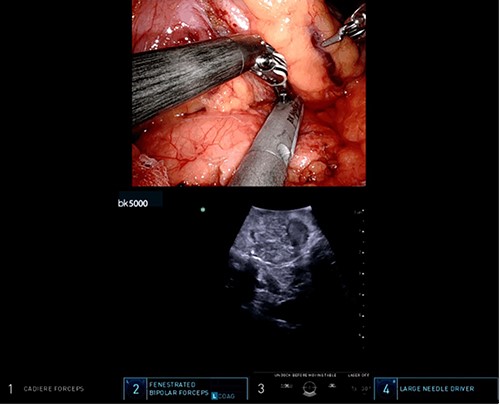

A robotic redo distal pancreatectomy was performed. Adhesions from the previous operation were taken down and the pancreatic stump was dissected. Samples of lymphatic tissue were sent for permanent pathology. An intraoperative ultrasound scan was done to localize the tumor and rule out concomitant lesions. A 2-cm nodule was found in the pancreatic stump (Fig. 3). With precise dissection, the gland was mobilized, reaching the confluence of the splenic and the portal vein. Afterward, the pancreatic stump was resected using a linear stapler (Fig. 4A and B). Once hemostasis was obtained, fibrin glue was applied to the section line and two drains were left close to the stump (Fig. 5). The patient was discharged on postoperative day 7. She developed a pancreatic biochemical leak that was managed conservatively. The histopathology analysis showed a grade 2, 1.3 cm well-differentiated neuroendocrine tumor with a low mitotic rate and Ki 67 index of 3%. After 16 months of follow-up, there was no evidence of recurrence.

Intraoperative ultrasound revealing a 2 cm lesion in the pancreatic stump.